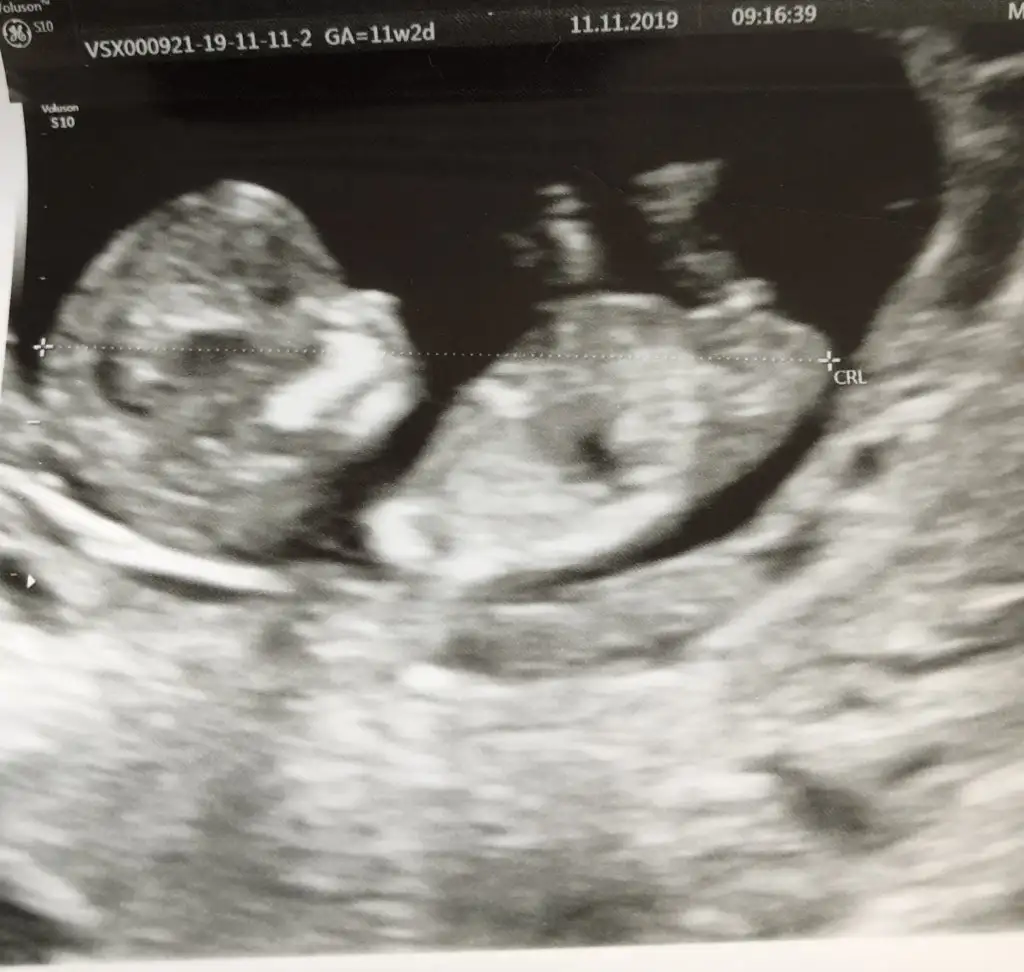

merhaba, ben de tahmin rica edebilir miyim? 11 hafta 2 günlük bebeğim :)

Teşekkür ederim yorumunuz için :) ikra meyra’dan da tahmin alabilir miyim?Erkek diyorum

KızEki Görüntüle 2553261